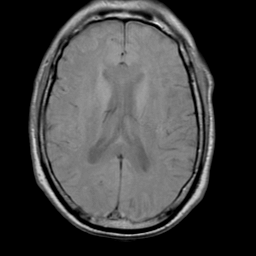

Meningioma, MR Study #2 -- Slice #11

[Home][Help][Clinical] Slice 11